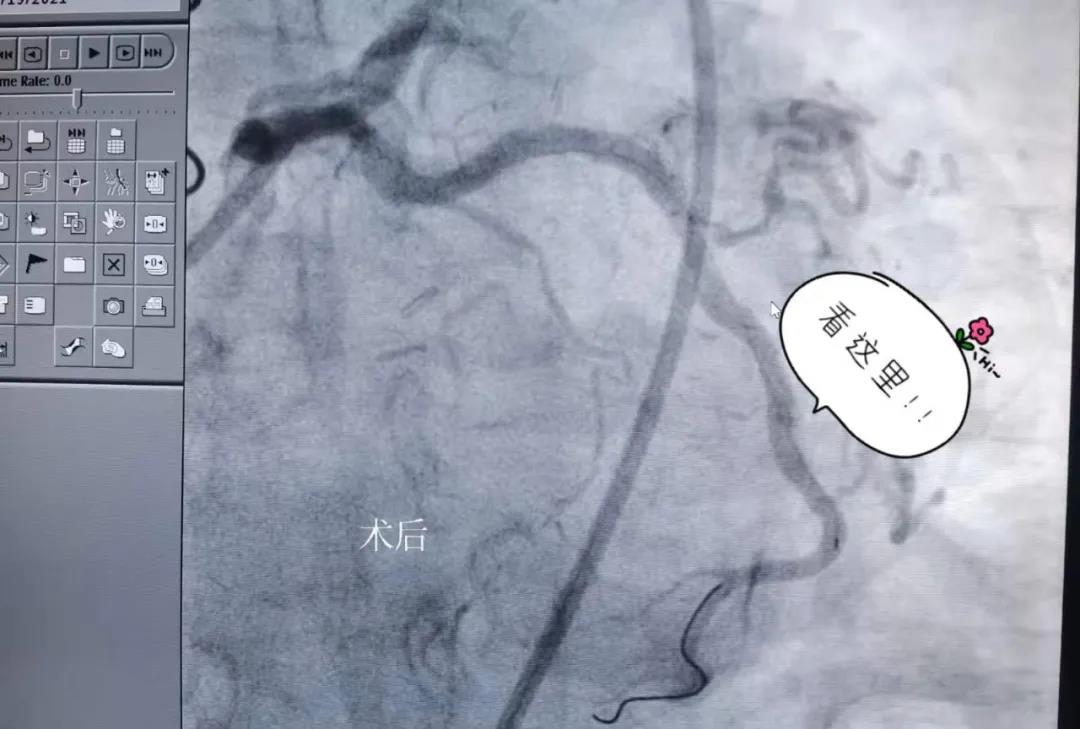

结果不出所料,桥血管果然又再次堵塞,再加之患者年纪也大了,面对如此复杂的情况该怎么办呢?最终徐元杰主任凭着丰富的经验,决定试行打通原血管,虽然手术风险很高,但是患者家属对两位主任也很信赖,同意徐主任的建议。历时两小时的手术非常成功,患者原血管被疏通,胸痛症状也随之消失。